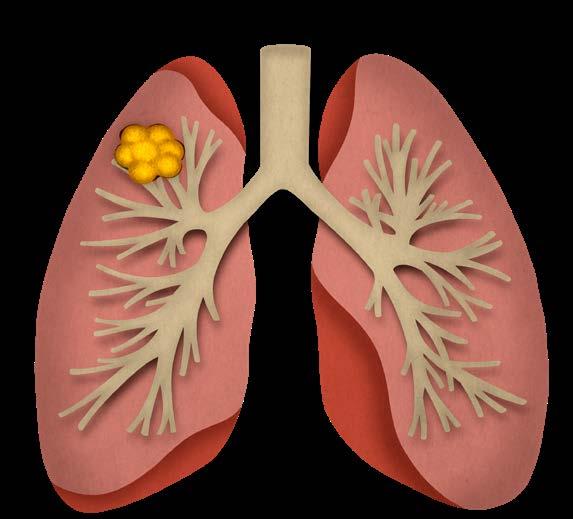

Mynd 6-1 Lítið lungnakrabbamein í hægra lunga (ör) sem fannst við skimun með tölvusneiðmyndum.

Með tilkomu tölvusneiðmyndatækni (TS) varð unnt að finna mun smærri hnúta í lungum en áður var mögulegt með hefðbundnum röntgenmyndum (mynd 6-1). Á síðustu áratugum hefur verið efnt til stórra framvirkra samstarfsverkefna, bæði í Bandaríkjunum og Evrópu. Fyrstu rannsóknir á skimun með TS voru gerðar í Japan og fyrsta alþjóðlega rannsóknin benti til þess að unnt væri að finna um